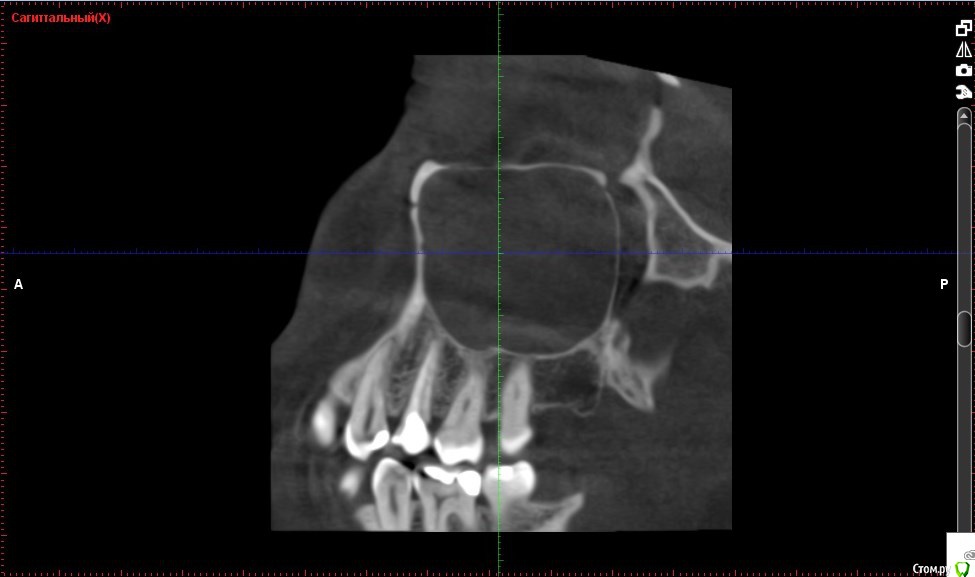

Verasss Опубликовано 8 октября, 2016 Автор Поделиться Опубликовано 8 октября, 2016 КТ от 08.09. Извините, что в таком виде, надо менять ОЗУ. Ссылка на комментарий

DmitrySH Опубликовано 8 октября, 2016 Поделиться Опубликовано 8 октября, 2016 В таком виде КТ малоинформативно. Но гайморита нет. Ссылка на комментарий

Verasss Опубликовано 28 октября, 2016 Автор Поделиться Опубликовано 28 октября, 2016 Добрый вечер! Ещё раз попытаюсь прикрепить скриншоты КТ от сентября. Если качество совсем не устраивает, подскажите, пожалуйста, какие сделать снимки?К сожалению, программа не позволяет вывести снимки на полный экран и заскриншотить в более хорошем качестве. Ссылка на комментарий

Verasss Опубликовано 28 октября, 2016 Автор Поделиться Опубликовано 28 октября, 2016 еще снимки Ссылка на комментарий

Verasss Опубликовано 28 октября, 2016 Автор Поделиться Опубликовано 28 октября, 2016 и еще Ссылка на комментарий

Verasss Опубликовано 23 ноября, 2016 Автор Поделиться Опубликовано 23 ноября, 2016 Сделала ещё 1 кт, спустя почти 2,5 месяца после первого. Посмотрите, пожалуйста, есть ли изменения? Напомню, что пункцию гайморовой мне сделали. Ссылка на комментарий